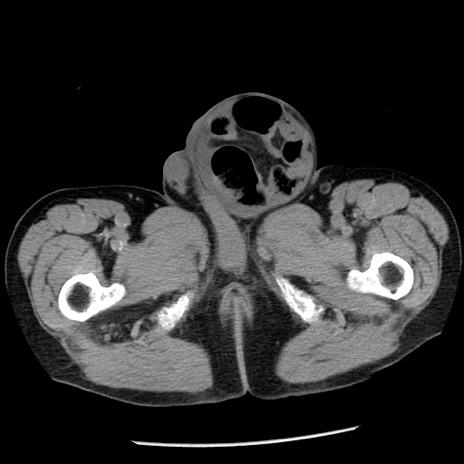

冠状断像

【症例】80歳代男性

【主訴】嘔吐

【現病歴】昨晩2回嘔吐あり、今朝になっても嘔吐あり。来院。

【既往歴】胃潰瘍

【身体所見】意識清明、BT 37.6℃、BP 166/95mmHg、HR 100bpm、SpO2 97%、腹部:平坦・軟、腸蠕動音聴取良好、圧痛なし。

【データ】WBC 21900、CRP 1.46